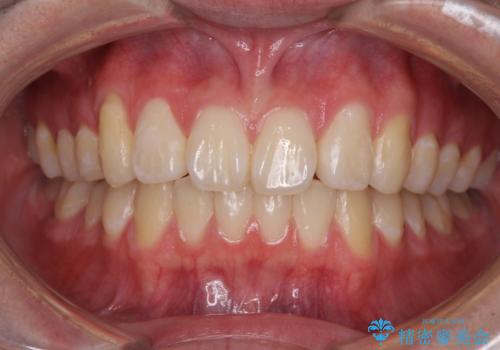

- 上の前歯が下唇に当たる感覚と奥歯の欠損を気にして来院された患者様です。

上顎前歯の突出感は、上顎全体が前方に位置していることが原因であったため、補助装置により上顎全体を後方に移動させることとしました。